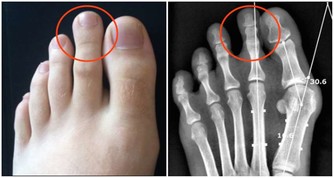

(1)痛風

痛風性關節炎發作前一定會有高尿酸血症期,但高尿酸血症不一定會發展為痛風,

從無症狀的高尿酸血症,到痛風性關節炎的首次發作需要5-10年時間;

血尿酸超過這個指標,說明離痛風更近了!

首發症狀常表現為夜間突發第一趾蹠關節疼痛難忍、局部紅腫、皮溫增高,其發病急驟,消退也快,,可在1週左右自行緩解,痛風易反復發作,可累及多個關節,並導致關節畸形。